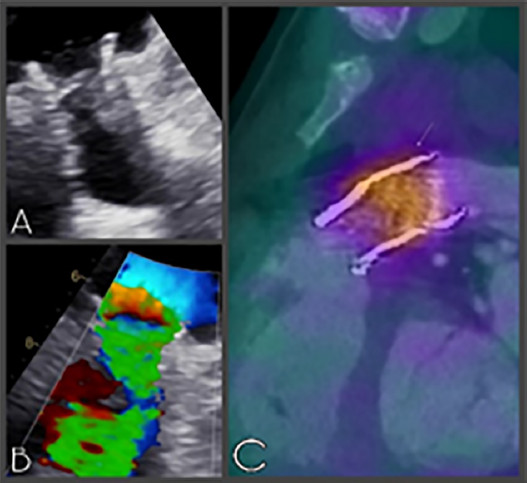

Como datos positivos se identificó en hemocultivos seriados al bacilo gran negativo Cardiobacterium del grupo HACEK; el eco Doppler color transesofágico evidenció un aumento marcado de los gradientes de la válvula pulmonar tipo Melody, con estructuras móviles compatibles con vegetaciones (Figura 1, A y B) y en el estudio de tomografía por emisión de positrones (PET/ TC) se vio un claro aumento de la captación de la región valvular pulmonar (Figura 1, C).

Con el diagnóstico clínico y por estudios complementarios se interpretó el cuadro febril como una endocarditis de la endoprótesis pulmonar, motivo por el cual se realizó una nueva cirugía para reemplazar la prótesis claramente infectada y el tracto de salida de la arteria pulmonar con un homoinjerto número 21. Se observo indemnidad de la válvula protésica aórtica, por lo que no se requirió reemplazo de esta (Figura 2, A, B y C).